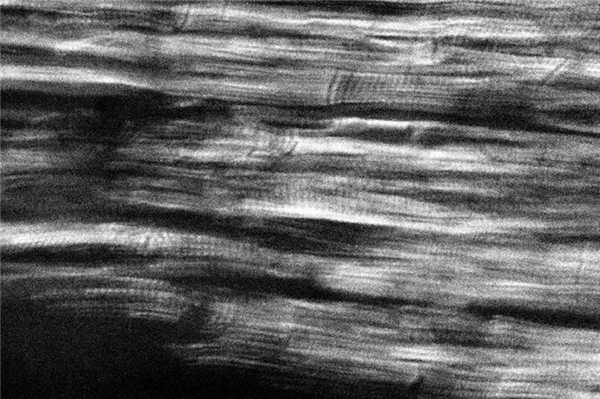

У погибших от изолированной черепно-мозговой травмы (ЧМТ), сопровождавшейся быстрым наступлением смерти вследствие повреждения ствола головного мозга, в поляризационной картине преобладает равномерное чередование анизотропных дисков в обоих желудочках сердца (см. рис.1), что соответствует физиологическому строению саркомера. При ЧМТ с непродолжительным премортальным периодом в миокарде левого и правого желудочка превалируют очаговые субсегментарные и сегментарные контрактуры кардиомиоцитов I степени (рис. 2). Рисунок 2. Контрактурные повреждения кардиомиоцитов I степени, очаговые субсегментарные контрактуры, трещины и диссоциация кардиомиоцитов при ЧМТ с переживанием. Поляризационная микроскопия. Ув. 500. Указанные изменения отражают минимальную степень гиперсокращения саркомеров. Независимо от темпа наступления смерти во всех случаях обнаруживали маркеры фибрилляции желудочков сердца, а показатели перикардиальной жидкости (концентрация глюкозы, натрия, калия, кальция и магния) указывали на отсутствие изменения углеводного и минерального обмена в миокарде [32—34]. Следовательно, у погибших по мозговому типу терминального состояния в случаях изолированной ЧМТ независимо от продолжительности премортального периода остановка сердца не связана с потерей сократительной способности миокарда. Она обусловлена нарушением его иннервации со стороны центральной нервной системы (ЦНС) с последующим возникновением фибрилляции желудочков сердца (фибрилляция желудочков центрального генеза).